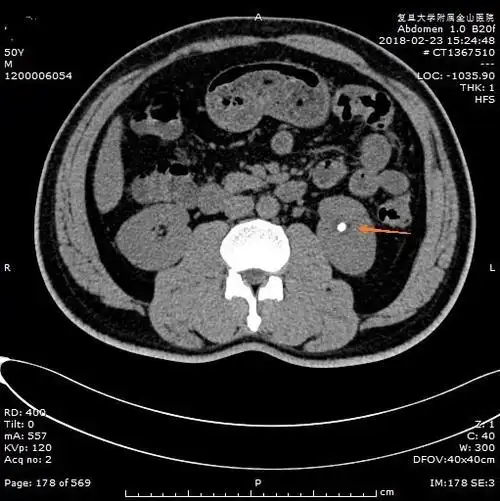

泌尿系统结石之肾结石ct表现

泌尿系统结石之肾结石ct表现 - 好大夫在线